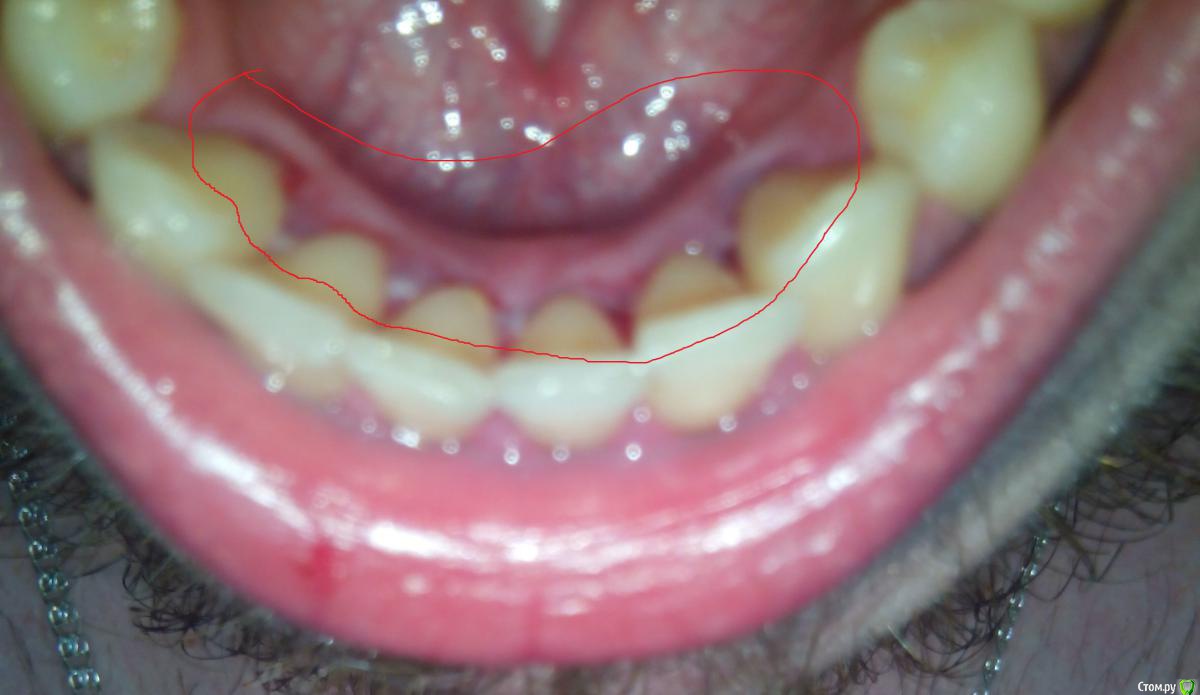

nikki_ewart Опубликовано 4 апреля, 2015 Поделиться Опубликовано 4 апреля, 2015 Доброго времени суток! Сегодня решил сделать удалить зубной камень, удалить то удалили, а дальше не сказали что делать. Дома заметил на деснах повреждения и что-то в виде гематом (обвел красным).Так же присутствует боль в зубах и реагирование на холодное/горячее. Что делать в данной случае?Извиняюсь за качество фото. Ссылка на комментарий